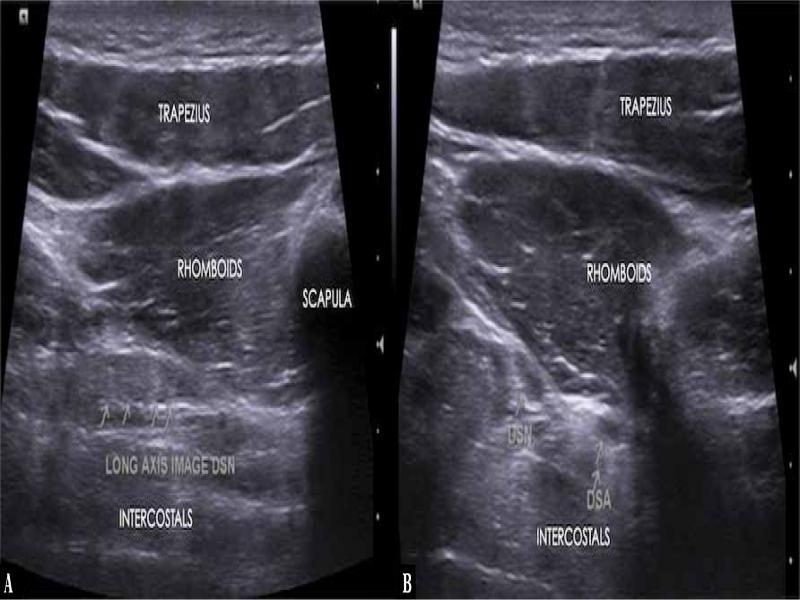

Fig. 1.

Longitudinal ( A ) and axial ( B ) ultrasound image showing the dorsal scapular nerve (DSN), dorsal scapular artery (DSA), and adjacent muscles

A 40-year-old male presented with 3 years’ history of unilateral localised pain with paraesthesia along the medial border of the left scapula. He was a painter and used to play overhead sports (badminton). His past medical history was unremarkable, and there was no history of trauma or surgery at this site. On clinical examination, there was no winging of the scapula. MRI (magnetic resonance imaging) of the thoracic spine and chest was unremarkable. The patient subsequently had a high-resolution ultrasound scan on Siemens Acuson NX3 Elite Ultrasound Machine using 5–16 linear probe, which demonstrated significant thickening of the dorsal scapular nerve at the level of the belly of the rhomboid major muscle, with narrowing and flattening distally (Fig. 1). On that basis, the diagnosis of DSNEN at the level of the rhomboid major muscle belly was made. In view of the chronicity of the symptoms and failure of physiotherapy, which had been performed for 2 months, hydrodissection of the dorsal scapular nerve was considered at the level of entrapment.